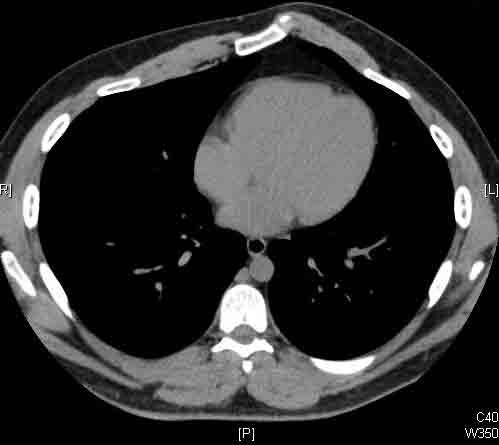

Here we present, as a paradigm of repair, the case of a 65 year old gentleman referred to our institution for an indolent mass in the left anterior chest wall. Repairs for other conditions follow the same rules. This mass had been stable in size for more than 12 months and the patient was prompted to seek medical attention as, after weight loss due to dieting, he felt the mass was uncomfortable while sleeping. Apart from coronary stenting for angina, the past medical history was unremarkable.

Computed tomography scan of the chest showed a mass protruding from the cortex of the third rib. A percutaneous core biopsy was non-diagnostic. We proceeded to an open incisional biopsy. This was reported as showing a spindle cell neoplasm. The patient was therefore scheduled, after multidisciplinary meeting discussion, for radical surgery.

At surgery, the mass was arising from the cortex of the third rib, and solid measuring 5x8 cm. There was no macroscopic involvement of the surrounding extra-thoracic musculature or of the underlying lung, the mass being confined to the rib and intercostal muscles. The patient underwent resection of the second to fourth ribs and the rhomboid muscle as well, in the attempt to get clear margin. The large antero-lateral defect was eventually reconstructed using 2 mouldable titanium bars. To prevent lung herniation through the defect, we reconstructed the layers anatomically using a biological patch (Veritas®). The final histopathology was a low grade sarcoma of the chest wall with clear resection margins.